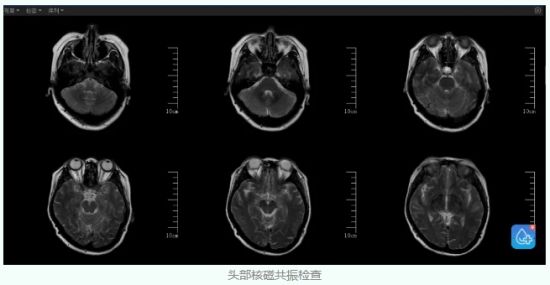

经过眼底检查发现,刘女士双侧的视神经乳头已经出现严重的水肿,这也是直接导致她双眼视力短期内迅速下降的根本原因。那么究竟是什么原因导致了双眼视乳头的这种病理改变呢?为了进一步明确视乳头水肿的“真凶”,杨钊医生为患者进行了头部核磁和腰穿检查。

头部核磁共振检查结果排除了颅内占位,但是静脉血管成像却显示出异常,刘女士左侧乙状窦显示明显狭窄,右侧横窦乙状窦显示不清。

经过磁共振最新的黑血技术检查,刘女士的右侧横窦和乙状窦是发育变异,而左侧的乙状窦出现了严重狭窄,这就是造成刘女士颅内压力增高的根本原因。